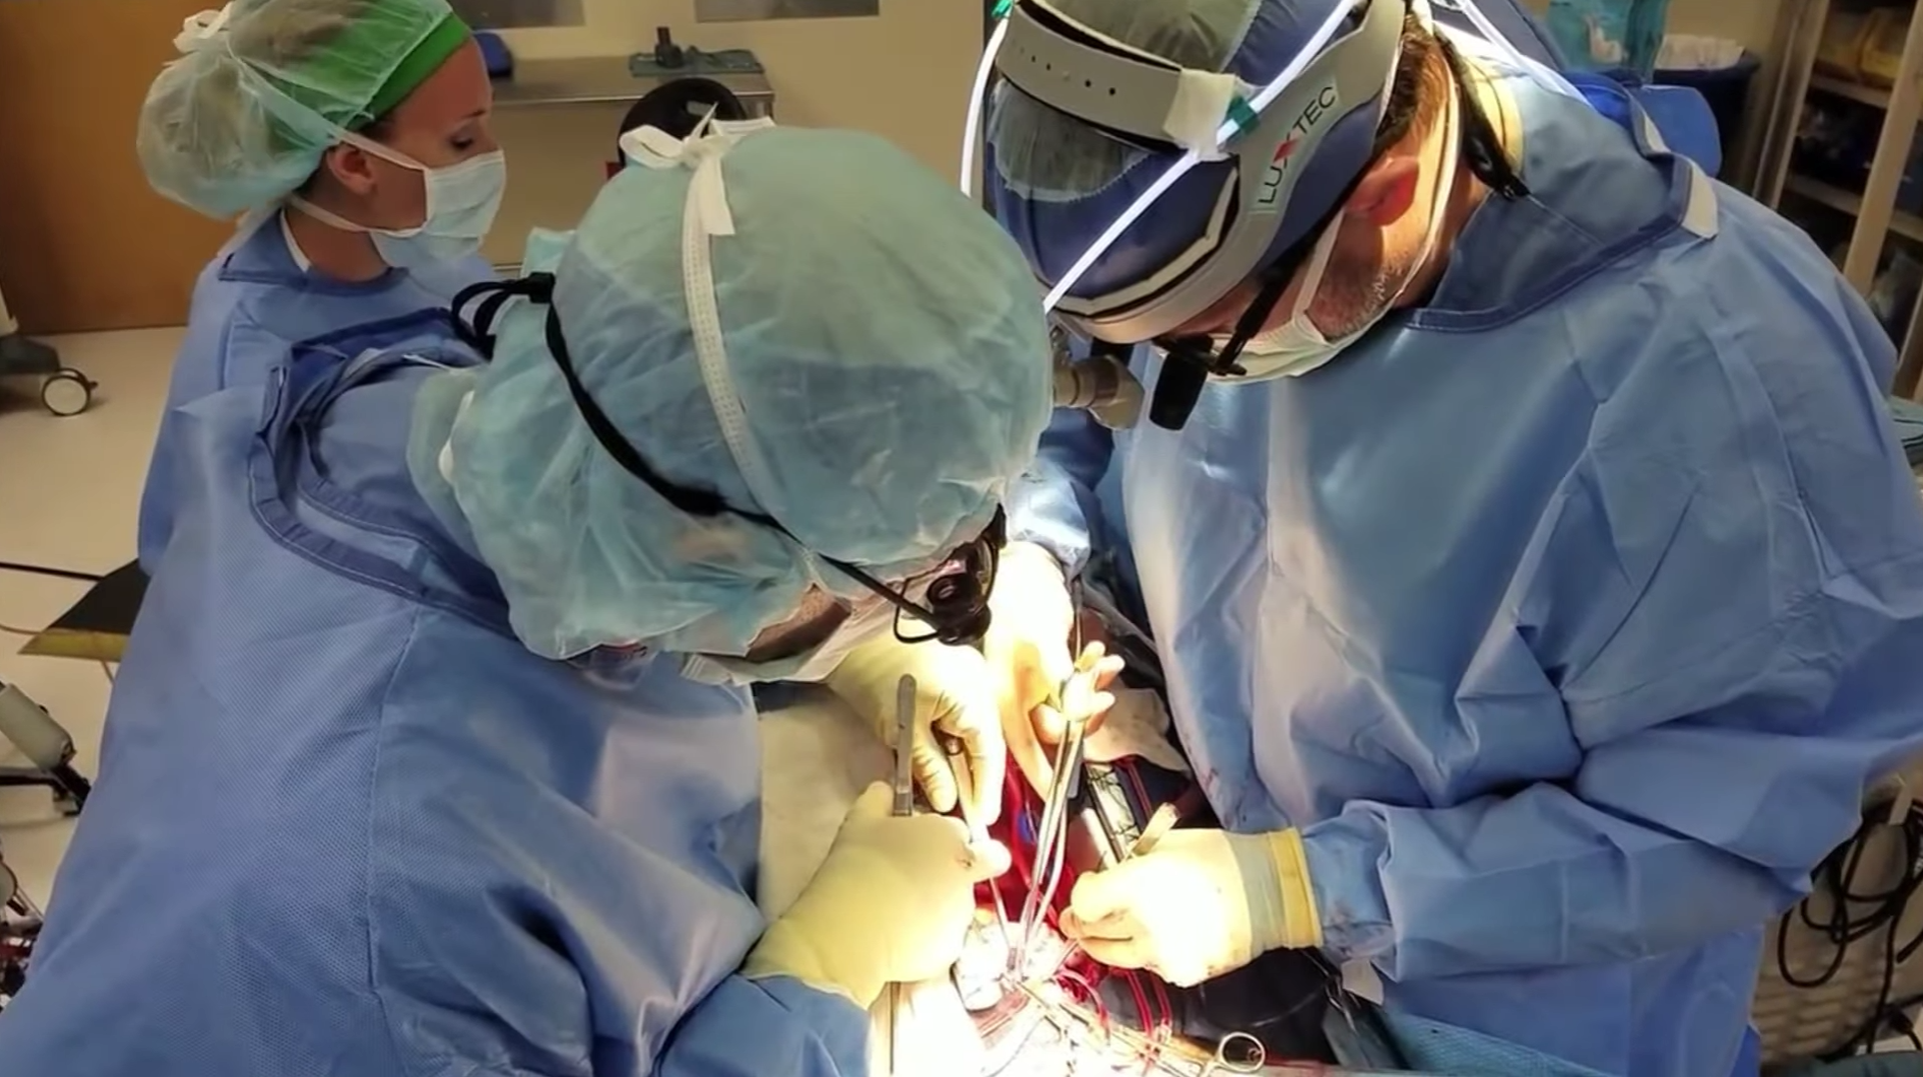

Cilt Grefti Uygulaması

Plastik Ve Rekonstrüktif Cerrahi

Ardian Kryeziu

Cilt Grefti Uygulaması

Plastik Ve Rekonstrüktif Cerrahi

Ardian Kryeziu

Cilt Grefti Uygulaması